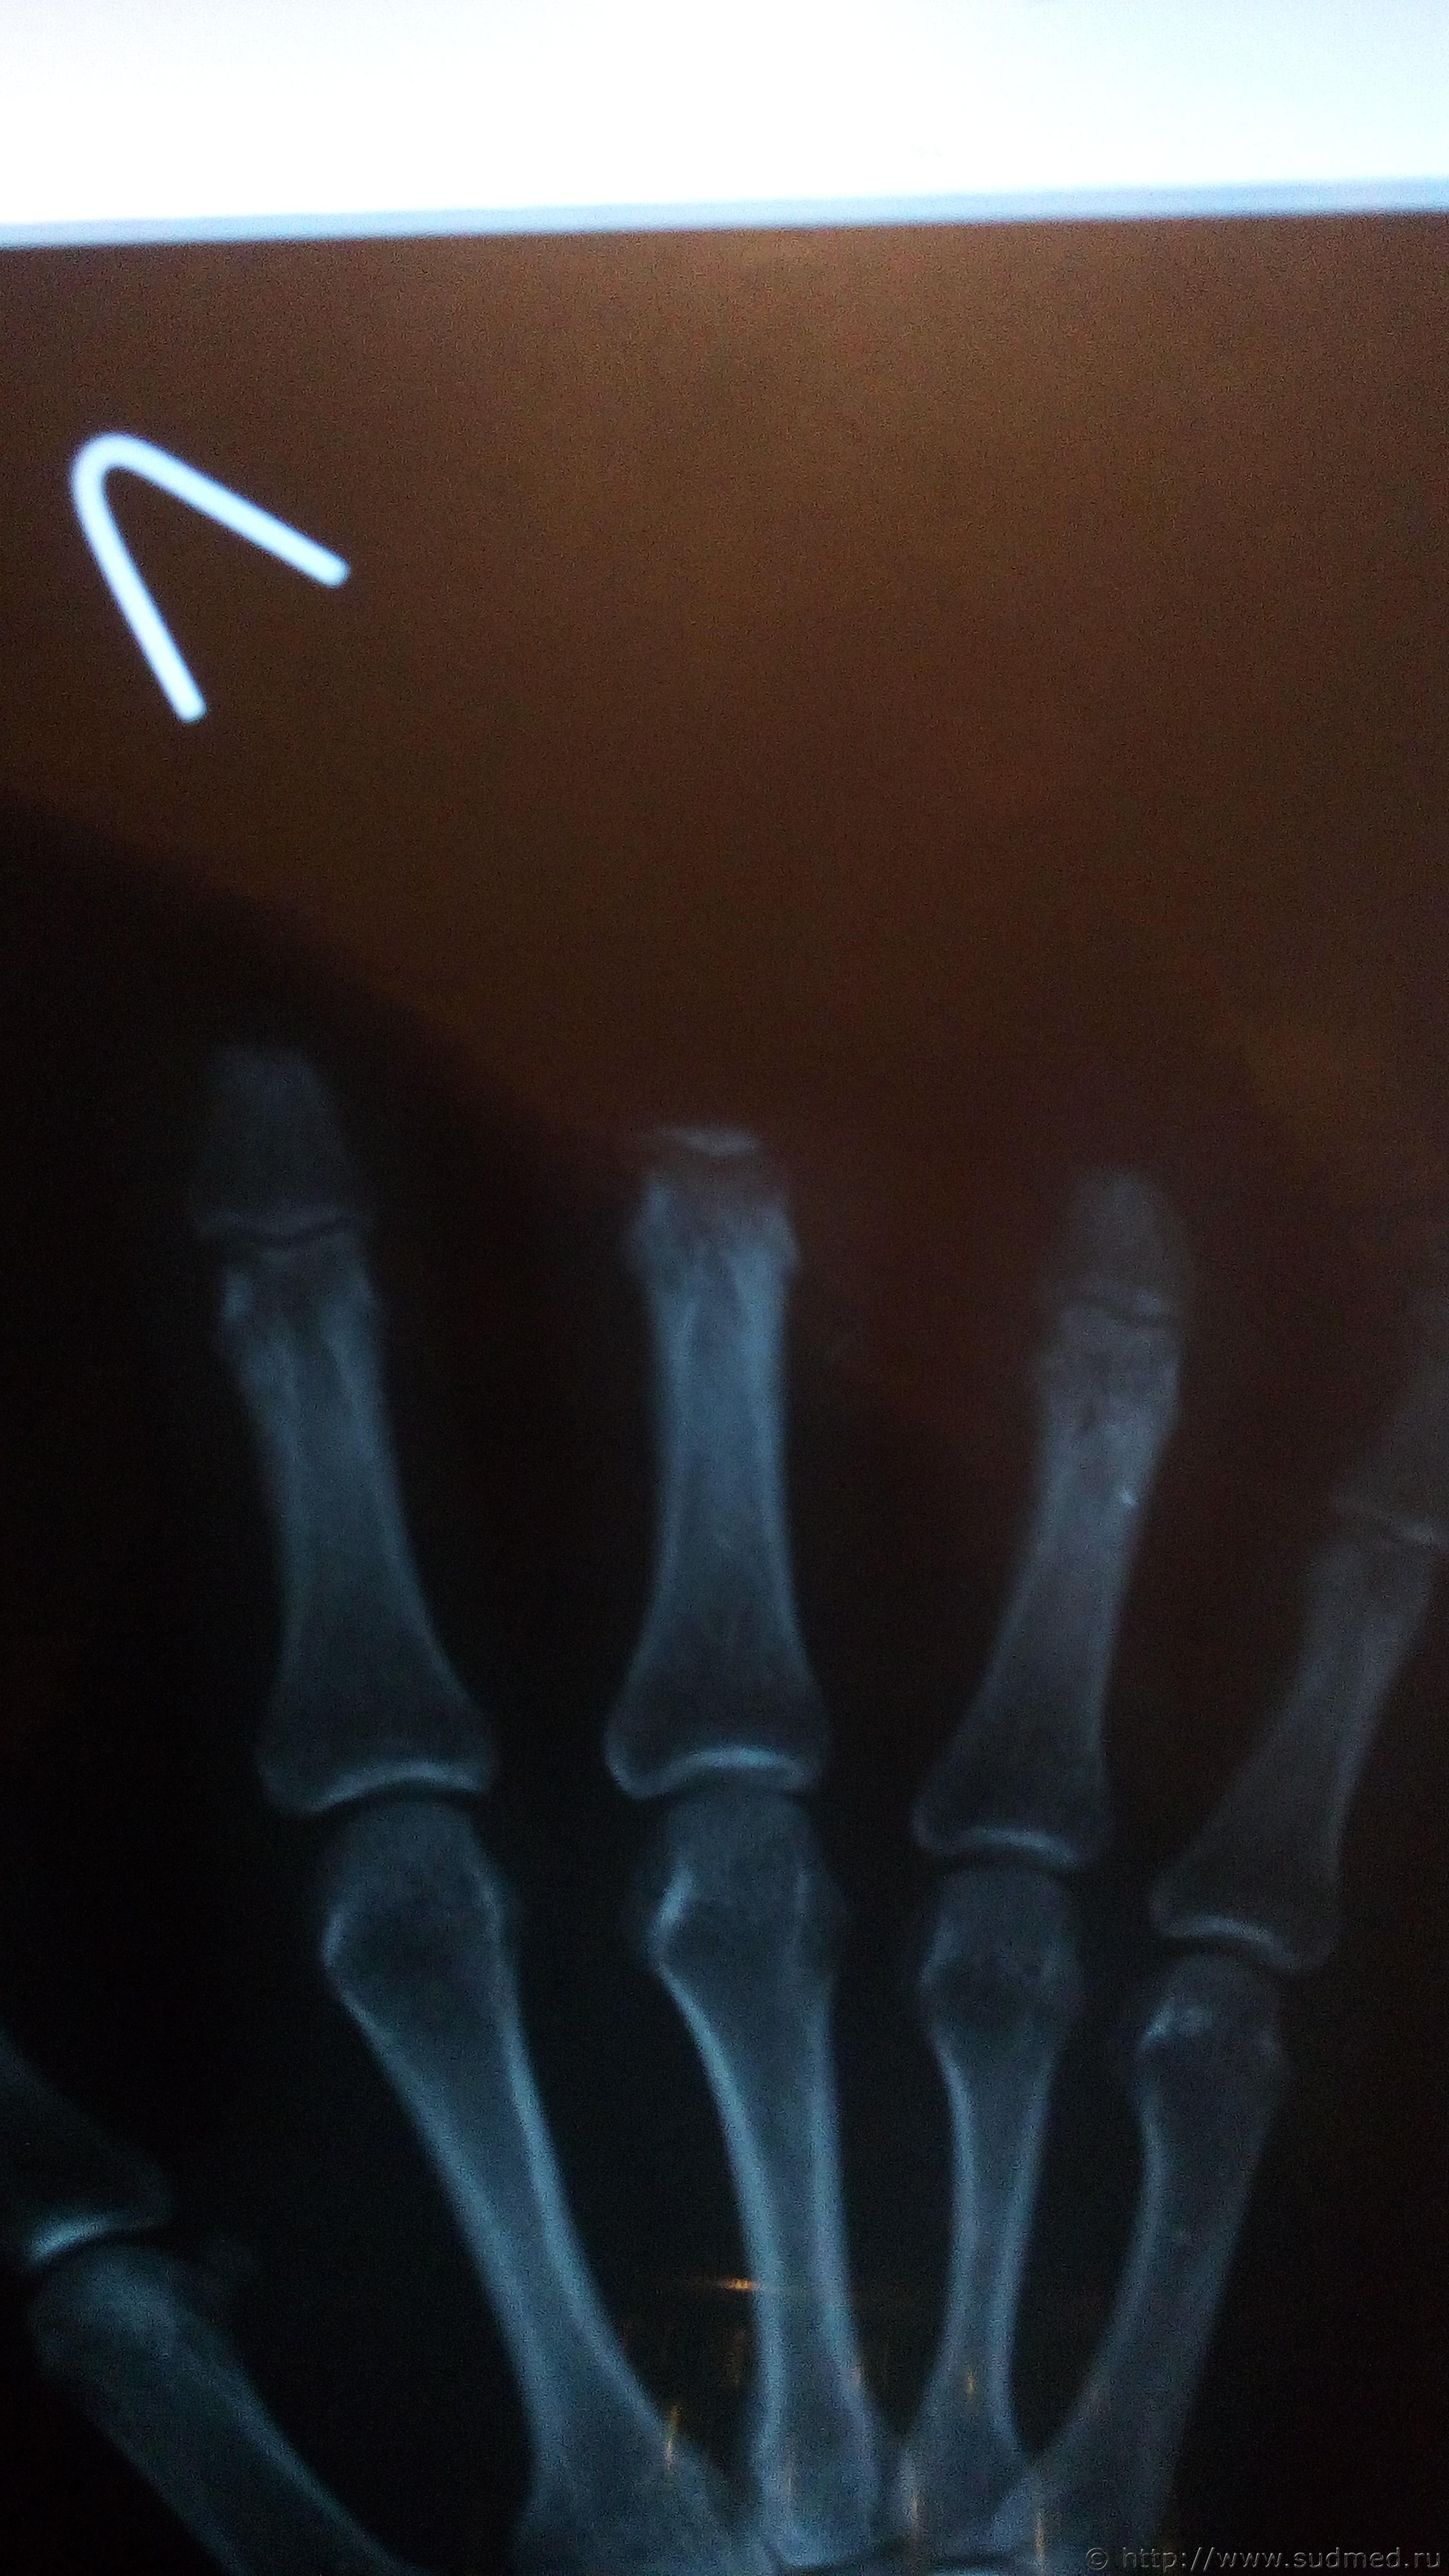

Здравствуйте работая на станке я получил травму:полный травматический отрыв 2-го пальца на уровне ногтевой фаланги,3-го пальца на уровне основания срединной фаланги,4-го пальца на уровне головки срединной фаланги левой кисти,скорую помощь мне вызывали отвезли в больницу самостоятельно спустя 15 минут от полученной травмы,была кровопотеря сопровождавшийся шоком и упадком артериального давления,потерю крови мне в больнице не компенсировали,пальцы не пришили(работодатель не привез их хотел сделать как бытовую травму)

Эскизы прикрепленных изображений

Судебная медицина - Прикрепленное изображение